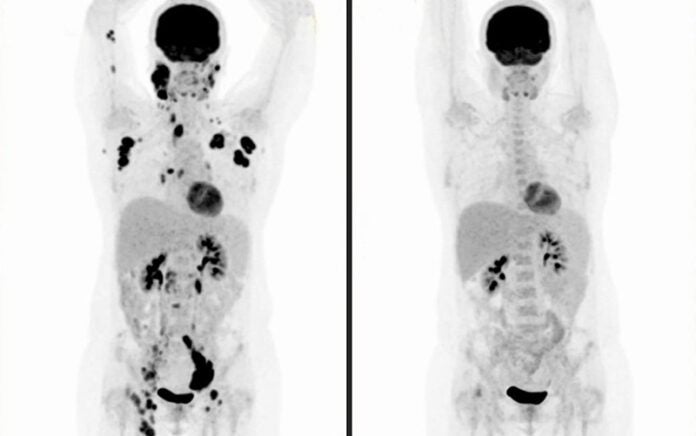

Car-T Cell: entenda terapia celular contra câncer aplicada de forma experimental — Foto: Editoria de Arte/g1